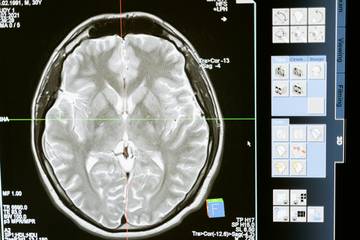

Sayangnya, tidak semua orang menyadari dampak buruk dari konsumsi video pendek secara berlebihan. Berbagai riset menunjukkan bahwa paparan konten singkat yang terus-menerus dapat memengaruhi kemampuan otak dalam jangka panjang. Pola ini membuat otak terbiasa dengan rangsangan cepat dan instan, sehingga sulit beradaptasi dengan aktivitas yang membutuhkan fokus mendalam.

Beberapa dampak yang kerap muncul antara lain penurunan fungsi kognitif, meningkatnya risiko kecanduan, hingga fenomena yang populer disebut brain rot atau “pembusukan otak”. Selain itu, kebiasaan ini juga dikaitkan dengan kesulitan mengambil keputusan, menurunnya daya konsentrasi, serta munculnya gangguan kecemasan. Jika dibiarkan, kondisi ini dapat memengaruhi produktivitas dan kesehatan mental secara keseluruhan.